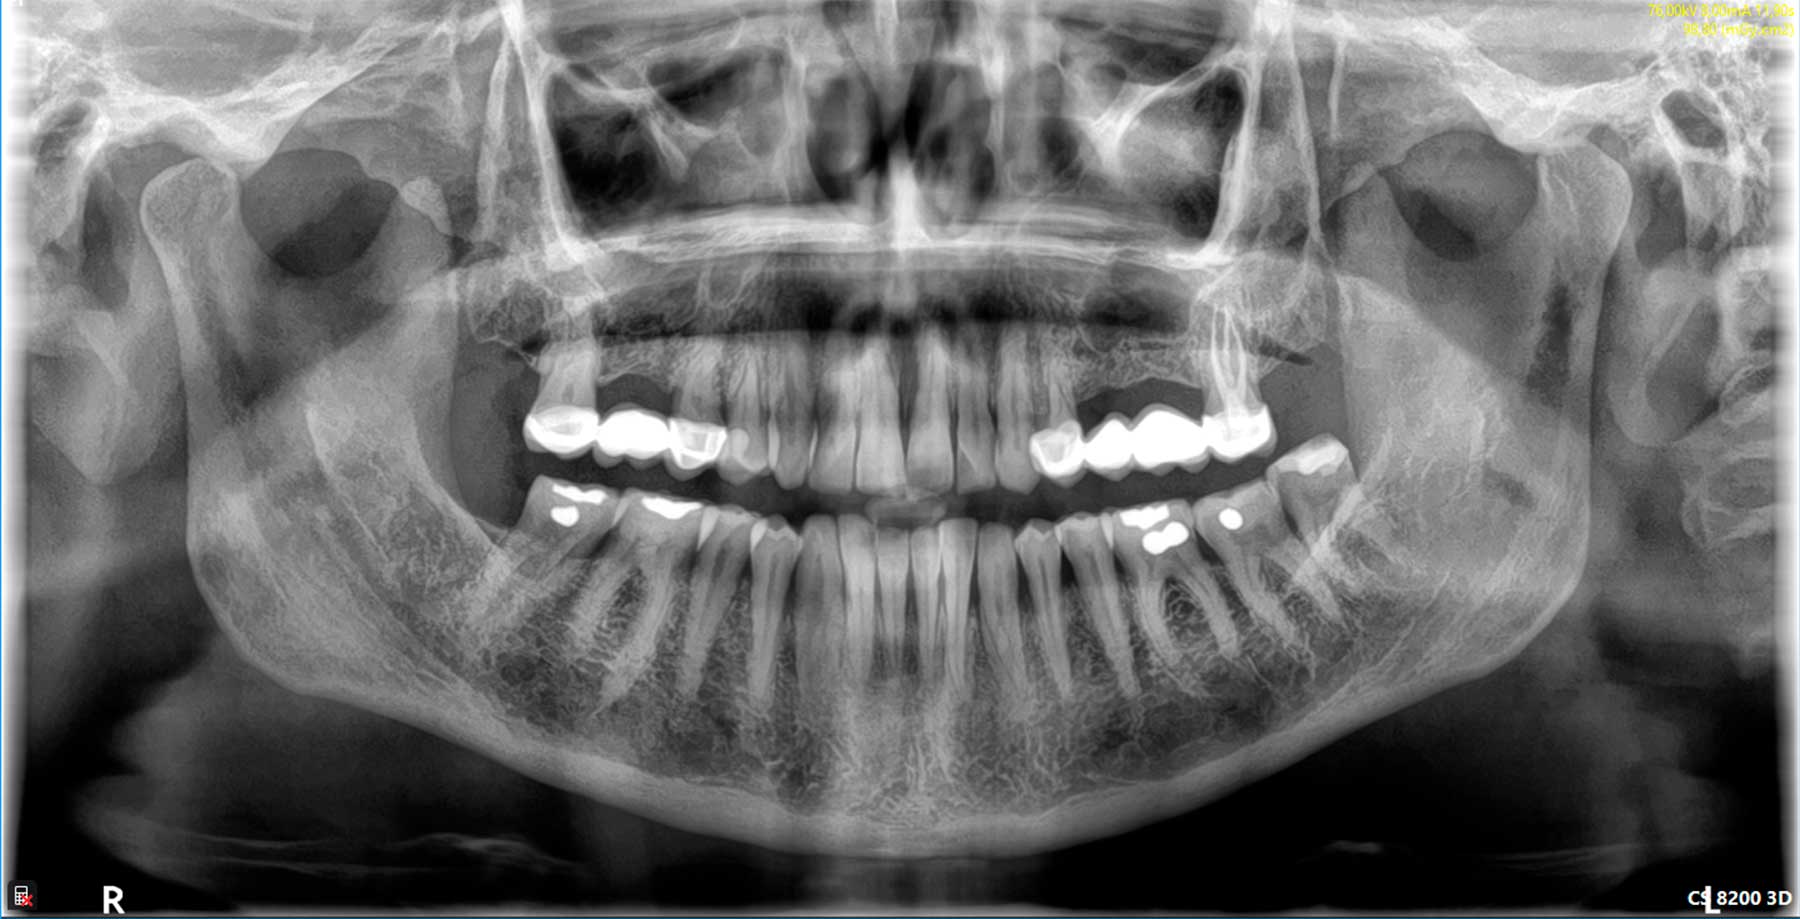

Radiología digital

Reduce en un 80% la radiación que recibe el paciente y permite obtener una imagen de forma instantánea, sin necesidad de revelado. Además, la tecnología digital permite la mejora de la imagen mediante técnicas informáticas. Hemos incorporado además, tecnología 3D mediante un sistema avanzado de Tomografía Computarizada de baja radiación CBCT (la de más baja radiación disponible en el mercado), lo que nos permite determinar la posibilidad de colocación de implantes en la primera visita diagnóstica, así como la detección de patologías asociadas a los maxilares.

Servicio de Tomografía computarizada CBCT, ortopantomografía, telerradiografía y radiografías de ATM al momento

Mediante la radiología digital de baja radiación, podemos valorar estructuras de interés odontológico o craneal, con imágenes 2D o 3D, según sea el caso.